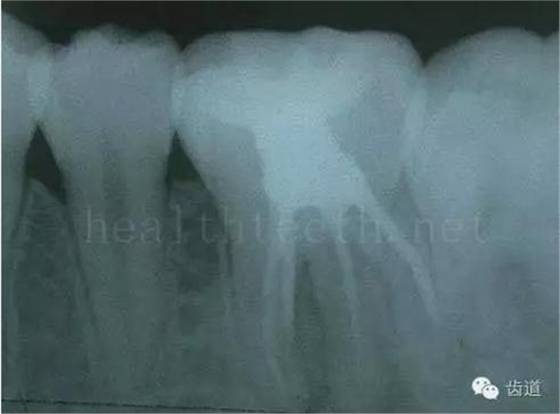

因?yàn)楸旧聿桓阏衬げ。占降牟±邢?,大多是同事收?/span> 頰粘膜扁平苔蘚 舌粘膜扁平苔蘚 舌緣創(chuàng)傷性潰瘍 長期戴活動義齒不當(dāng)或是戴不良修復(fù)義齒造成的口腔粘膜潰瘍,應(yīng)該引起高度警惕,因?yàn)檫@種潰瘍?nèi)菀装┳?/span> 黑毛舌 舌息肉,該患者同時伴有胃、食管息肉,后來看內(nèi)科了,具體情況不詳 四、孩子的牙齒問題 乳牙未退,牙根穿出牙齦對上唇粘膜造成刺激 乳牙滯留,也是孩子在退牙過程中最容易遇到的問題 五、牙齒發(fā)育上的問題 變色牙 氟斑牙 釉質(zhì)發(fā)育不全 四環(huán)素牙 牙神經(jīng)治療后的牙齒變色 10歲孩子剛剛萌出的牙齒變色 2、埋伏牙 左上乳3滯留,恒3未見萌出,曲面斷層片顯示牙齒埋伏 通過CT片確定埋伏牙齒具體的位置,顯示距離左側(cè)上頜竇很近,偏唇側(cè),這為手術(shù)定位提供了方便 手術(shù)中切斷、完整拔出,未損傷上頜竇 其他埋伏牙 3、多生牙 病例1 病例2 病例3,同時多生兩顆牙齒 4、各種畸形牙 畸形過小牙 融合牙:恒牙和乳牙都可以發(fā)生融合的情況(兩顆牙齒長在了一起) 畸形中央尖:在牙齒的中央,兩個牙尖之間又多長出一個牙尖,由于進(jìn)食的磨耗很容易造成磨穿,神經(jīng)就會與外界相通,出現(xiàn)牙髓炎的癥狀 六、牙齒的外傷 牙冠折斷 牙根折斷 烤瓷牙打樁修復(fù)后牙根折斷 外傷后牙齒的全脫位,應(yīng)該保留牙齒盡早做再植手術(shù) 七、牙齒的慢性損傷 牙頸部楔狀缺損 牙冠劈裂及完整拔除后的情況 牙根縱裂及拔除后的情況 牙隱裂,牙齒表面有肉眼看不到的裂紋,細(xì)菌通過其進(jìn)入牙髓,容易出現(xiàn)牙髓炎癥狀,嚴(yán)重可以造成牙齒的劈裂 這是一位來中國學(xué)習(xí)的俄羅斯大學(xué)生的牙齒,已經(jīng)做過了根管治療,牙齒咬合面有隱裂,通過鋼絲結(jié)扎固定,做鑄造金屬冠修復(fù)。 八、牙髓炎、根尖周炎 下面圖片都是慢性根尖周炎的病例,有了齲齒,進(jìn)一步發(fā)展就是牙髓炎,如果此時沒有得到及時的治療,疾病會逐漸發(fā)展破壞到根尖的骨質(zhì),將骨質(zhì)破壞后就在牙齦上出現(xiàn)一個膿瘺,此時患者不再感覺到牙齒的疼痛了,往往忽視了治療,但是這種不痛并不是疾病好轉(zhuǎn)了,而是因?yàn)榧膊〉难仔詽B出得到了引流,這個膿瘺會出現(xiàn)有時候變大了,有時候又變小了,但是如果不治療是不會自己愈合的,只有經(jīng)過完善的根管治療后才有好轉(zhuǎn)的可能,但是在疾病的治療中時間是起決定作用的,時間拖得越晚,好轉(zhuǎn)的可能性越小,經(jīng)過根管治療后如果膿瘺還是沒有消失,就需要做根尖刮治術(shù),如果仍然沒有好轉(zhuǎn),就只能做根尖切除術(shù)了,這對牙齒的穩(wěn)固是不利的。下面圖片中在膿瘺中插入了一個牙膠尖,是我們做根管充填用的材料,是非常軟的,就是在口腔牙齦瘺管的地方插進(jìn)去,通過拍牙片可以清晰地看到它到達(dá)的位置,從而確定發(fā)病的牙齒,此處是為了讓大家看得更清楚。 門牙兩個膿瘺 烤瓷牙修復(fù)后牙齦出現(xiàn)兩個膿瘺,插入牙膠尖,牙片顯示牙膠尖到達(dá)的位置就是根尖炎癥的位置,根尖骨質(zhì)密度降低(發(fā)黑的地方) 牙齒根尖膿瘺,治療前、中、后的圖片對照,完善根管治療后膿瘺明顯消失了 牙髓炎和根尖炎治療的關(guān)鍵就是根管治療 合格的根管充填治療 不良的根管充填治療 九、關(guān)于智齒(第八顆牙) 四顆長不出來的智齒 智齒反復(fù)發(fā)炎造成的頰瘺,膿腫切開引流后面部會留疤 智齒造成的頜骨囊腫,手術(shù)切除后需要植骨 十、各種錯合畸形 開合 深覆合 深覆蓋,上頜前突 反合(地包天) 牙齒排列擁擠 來源:牙醫(yī)愛看的 KQ88口腔醫(yī)學(xué)網(wǎng)